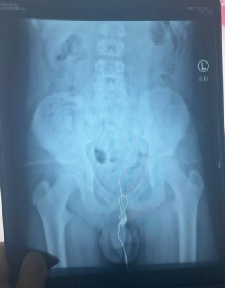

这名12岁男孩正处于对世界充满好奇的年纪,尤其对自己的身体结构满是懵懂的探索欲。某天玩耍时,他突发奇想,拿着一根较长的数据线尝试塞入尿道,可这一“试探”瞬间酿成大麻烦——数据线一端滑入膀胱,尿道球部却意外打结,往外拔被死死卡住,往膀胱推又找不到受力点,硬生生“赖”在尿道里。

孩子疼得直咧嘴,排尿时剧痛难忍还出现血尿,父母发现后立刻带他直奔医院。接诊的张林琳教授团队检查后也捏了把汗:“尿道异物本就危险,还打了结,稍有不慎就会损伤黏膜、引发感染。”

紧急研讨后,医护团队敲定最优方案——球部尿道切开术。张林琳教授解释:“男性尿道球部最宽大、血运丰富,在这里切开取异物,术后尿道狭窄的概率更低,能最大程度减少对孩子未来的影响。”

手术中,医护人员小心翼翼操作,避免对孩子娇嫩的尿道组织造成二次伤害,最终成功将数据线完整取出。看着这根让孩子遭罪的数据线,父母既心疼又懊悔:“早知道就多管管他,早该早点给他讲这些知识。”